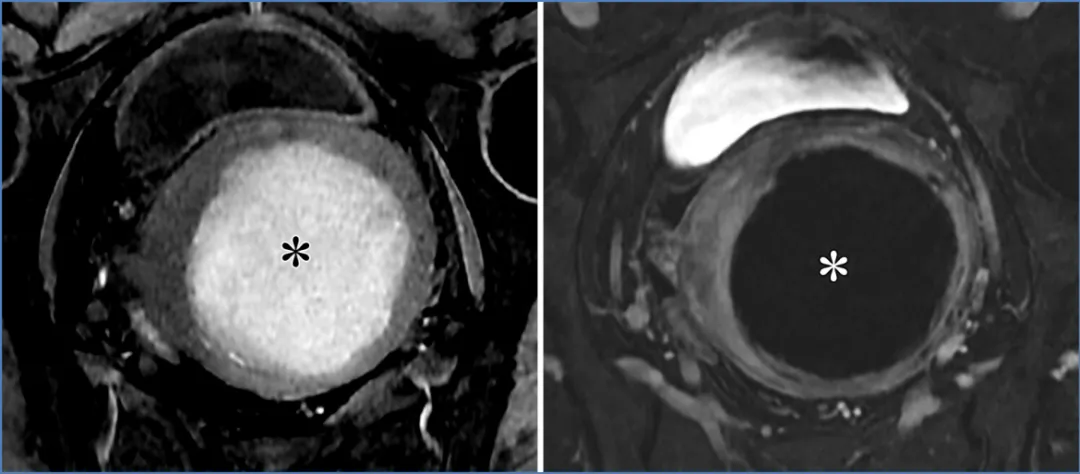

高级别浆液性卵巢癌(HGSOC)是最常见的侵袭性上皮肿瘤,也是总体上最常见的卵巢癌(36)。它通常发生在绝经后女性中,且与CA-125水平升高相关。高级别浆液性卵巢癌的一个风险因素是遗传性乳腺癌和卵巢癌综合征,该综合征主要由生殖系BRCA1/2突变引起,会导致发病年龄提前(54)。高级别浆液性卵巢癌常表现为双侧实性或囊性病变,伴有大体积的T2非低信号/弥散加权成像非低信号实性组织、腹膜种植灶、腹水,有时还有淋巴结肿大,这反映出由于缺乏早期症状且腹膜扩散迅速,其就诊时通常已处于晚期(图31)(36)。

图31. 一位52岁女性患者的高级别浆液性卵巢癌,该患者有腹痛、腹胀症状,且血清CA-125水平升高。轴位T2加权像(A)、高b值弥散加权像(B)和对比增强脂肪抑制T1加权像(C)显示双侧附件囊性病变,其中的实性组织(*)在T2加权像(A)上呈中等信号强度,在高b值弥散加权像(B)上呈高信号强度,且在对比增强像(C)上有强化。此外,还可见后陷凹的腹膜种植灶(黑色箭头)、腹水以及右侧盆腔淋巴结肿大(白色箭头)。

若已知存在原发性恶性肿瘤,应考虑卵巢转移瘤的可能,但卵巢转移瘤也可能是隐匿性原发性恶性肿瘤的首次表现(36)。最常见的原发部位包括结肠或子宫内膜腺癌,其次是胃、乳腺、阑尾和胰胆管腺癌。卵巢转移瘤患者通常比原发性浸润性上皮性卵巢肿瘤患者更年轻,且病变通常为双侧,生长迅速。库肯勃瘤是卵巢转移瘤的一种亚型,约占病例的50%,起源于具有分泌黏液的印戒细胞的腺癌(78)。它们通常起源于胃,但也可能源于其他部位,包括结肠、阑尾和乳腺(83)。卵巢转移瘤通常表现为双侧快速增大的实性或囊性病变,实性部分在T2加权成像上呈非低信号,在弥散加权成像上也呈非低信号。在库肯勃瘤中,囊性成分代表肿瘤细胞分泌的黏液(图33)(36,78)。

图33. 一名44岁女性患者的胃印戒细胞腺癌双侧卵巢转移(库肯勃瘤)。(A)轴位T2加权像显示右侧卵巢(RO)被带有不均质实性组织的囊性病变取代,左侧卵巢(LO)被不均质实性病变取代。右侧肿块中T2高信号的囊性部分(*)是由肿瘤细胞分泌的黏液所致。(B、C)轴位高b值扩散加权像(B)显示高信号,对应的轴位ADC图(C)显示低信号,与两个肿块中的弥散受限(箭头)一致。(D)轴位对比增强脂肪抑制T1加权像显示双侧卵巢肿块中的实性组织强化。